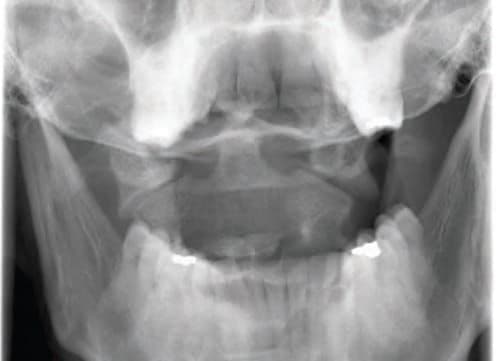

Приблизно 60% переломів С2 охоплюють зубоподібний відросток осьового хребця, кістковий виступ у формі кілочка, який виступає вгору і зазвичай перебуває в контакті з передньою дугою С1. Зубоподібний відросток осьового хребця переважно утримує на місці поперечна зв’язка. Переломи зубоподібного відростка I типу зазвичай охоплюють його верхівку і бувають відносно рідко. Переломи зубоподібного відростка II типу виникають у ділянці його основи і трапляються найчастіше (Зобр. 7-5).

Зобр. 7-5 Перелом зуба осьового хребця. Комп’ютерна томографія перелому зуба ІІ типу, який відбувається через основу зуба.

У дітей віком до 6 років епіфіз може виступати й нагадувати перелом на цьому рівні. Переломи зубоподібного відростка  III типу виникають біля його основи і поширюються косо в тіло осьового хребця.